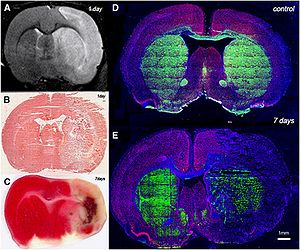

MRI-Only Based Radiotherapy Treatment Planning for the Rat Brain on a Small Animal Radiation Research Platform (SARRP)

Publication: PLoS One. 2015 Dec 3;10(12):e0143821. PMID: 26633302 | PDF Authors: Gutierrez S, Descamps B, Vanhove C. Institution: Medical Image and Signal Processing Group, Ghent University-iMinds Medical IT department, Ghent, Belgium. Background/Purpose: Computed tomography (CT) is the standard imaging modality in radiation therapy treatment planning (RTP). However, magnetic resonance (MR) imaging provides superior soft tissue contrast, increasing the precision of target volume selection. We present MR-only based RTP for a rat brain on a small animal radiation research platform (SARRP) using probabilistic voxel classification with multiple MR sequences. Six rat heads were imaged, each with one CT and five MR sequences. The MR sequences were: T1-weighted, T2-weighted, zero-echo time (ZTE), and two ultra-short echo time sequences with 20 μs (UTE1) and 2 ms (UTE2) echo times. CT data were manually segmented into air, soft tissue, and bone to obtain the RTP reference. Bias field corrected MR images were automatically segmented into the same tissue classes using a fuzzy c-means segmentation algorithm with multiple images as input. Similarities between segmented CT and automatic segmented MR (ASMR) images were evaluated using Dice coefficient. Three ASMR images with high similarity index were used for further RTP. Three beam arrangements were investigated. Dose distributions were compared by analysing dose volume histograms. The highest Dice coefficients were obtained for the ZTE-UTE2 combination and for the T1-UTE1-T2 combination when ZTE was unavailable. Both combinations, along with UTE1-UTE2, often used to generate ASMR images, were used for further RTP. Using 1 beam, MR based RTP underestimated the dose to be delivered to the target (range: 1.4%-7.6%). When more complex beam configurations were used, the calculated dose using the ZTE-UTE2 combination was the most accurate, with 0.7% deviation from CT, compared to 0.8% for T1-UTE1-T2 and 1.7% for UTE1-UTE2. The presented MR-only based workflow for RTP on a SARRP enables both accurate organ delineation and dose calculations using multiple MR sequences. This method can be useful in longitudinal studies where CT's cumulative radiation dose might contribute to the total dose. |

Illustration of a CB-CT and five MR images of the same animal. a) Coronal CB-CT image and (b)-(f) biased field corrected and masked coronal MR images using a T1-weighted (b), T2-weighted (c), ZTE (d), UTE1 (e) and UTE2 (f) sequence. All CB-CT images were first co-registered using 3D Slicer version 3.6.3 by rigid body transformations using normalized mutual information. |